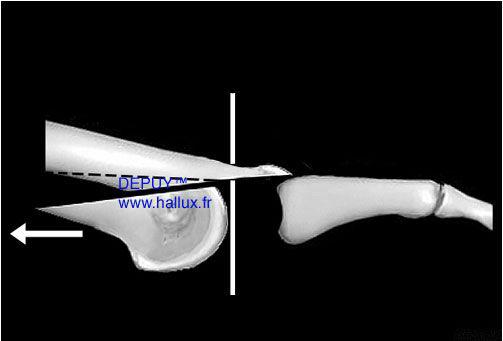

CETTE OSTEOTOMIE METATRSIENNE

PEUT ETRE REALISÉE EN PERCUTANÉ.

par une incision puctiforme, de 3 à 5 mm. On utilise pour sectionner l'os,une fraise motorisée, très fine avec un moteur rotatif tournant à vitesse lente (500 à 2000 tours/minute) pour éviter la brûlure des tissus. L'ostéotomie et le recul de la tête du métatarsien, est de façon encore mois aggressive.

Les cicatrices sont alors minimes.

Le geste chirurgical est guidé par une appareil de radsiocopie (amplificateur de brillance).